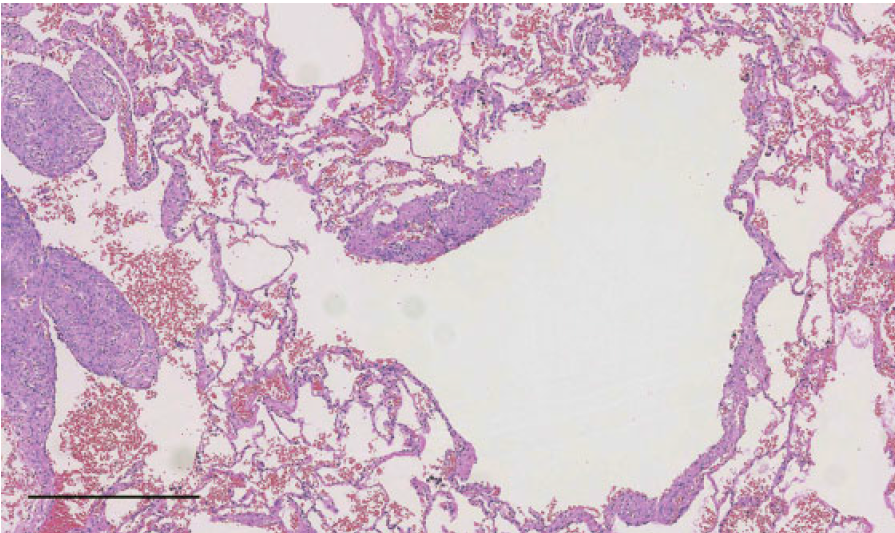

淋巴管肌瘤病的病理特征是肺部囊性改变、LAM细胞肿瘤样增生,免疫组化:HMB45, SMA, ER, PR;分子特征:TSC2突变。